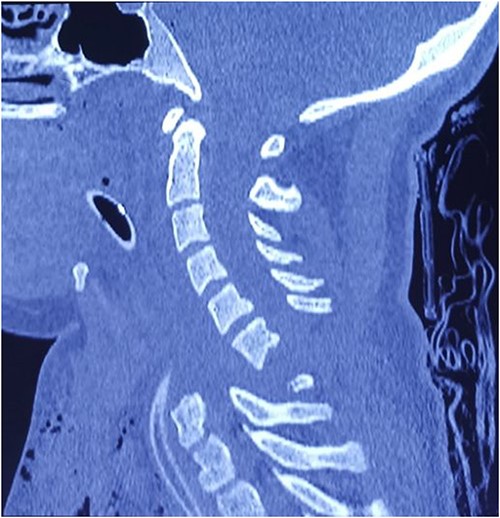

Computed tomography revealed complete traumatic dislocation of C6/C7 with consequent transection of the spinal cord (Figs 1 and 2).

Computed tomography finding (3D reconstruction): C6/C7 dislocation.